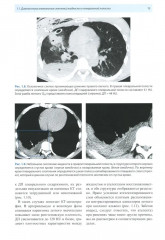

💳 Оплатить за товар можно при получении 🇰🇿 Есть бесплатная доставка по Казахстану от 1 дня 🎁 Копите бонусы с каждой покупки Издание содержит результаты анализа многочисленных рентгенологических и КТ-исследований, выполненных с целью диагностики огнестрельных ранений грудной полости. Уделено большое внимание описанию макроморфологических изменений при современной огнестрельной травме, отображаемых при КТ, и патогенезу их развития. Описана рентгеновская семиотика ранений легких, пищевода, сердца, сосудов, а также наиболее грозных осложнений, встречающихся при ранениях этих органов. Наряду с обычным рентгенологическим методом и КТ показаны возможности современных информативных медицинских технологий в диагностике боевой травмы. Книга иллюстрирована большим количеством рентгенограмм и КТ-изображений. Авторы надеются, что предлагаемая монография будет интересна врачам-рентгенологам, а также врачам других специальностей, занимающимся проблемами диагностики и лечения огнестрельных ранений. |